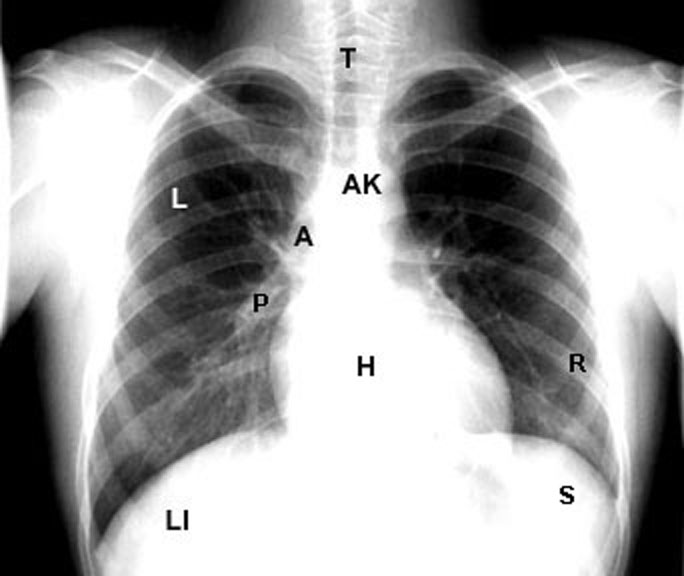

clinical images Chest X ray PA normal lebelled What Does A Normal Chest X Ray Look Like  There are no visible nodules, tumors or masses. This image shows a normal chest. Doctors typically use this procedure to help diagnose breathing difficulties, a bad or. Darker colors indicate less dense material, and lighter colors indicate more dense material. What Does A Normal Chest X Ray Look Like.

What Does A Normal Chest X Ray Look Like . Darker colors indicate less dense material, and lighter colors indicate more dense material. Doctors typically use this procedure to help diagnose breathing difficulties, a bad or. This image shows a normal chest. There are no visible nodules, tumors or masses.